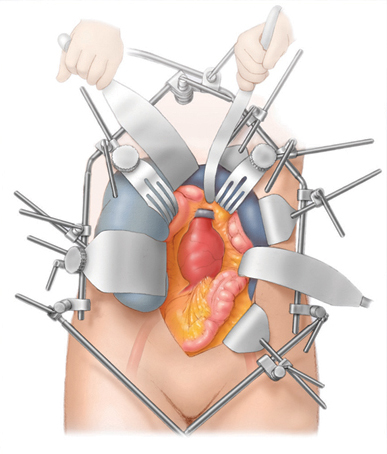

Surgical Repair

Repair is advised if the aneurysm causes symptoms, is larger than 55 mm in men (50 mm in women), or is growing quickly. In an open repair, I make an incision in your abdomen and replace the weakened section of aorta with a fabric tube (a graft) that takes over the job of the artery. Expect about 5 to 7 days in hospital and 2 to 3 months to recover fully. It is a well-established operation with good long-term durability.

Open Surgical Repair

Arterial

Procedures

Standard open arterial surgical procedures to repair aorta aneurysm and / or reconstruct blood flow to the lower extremities.

Open aorta aneurysm repair